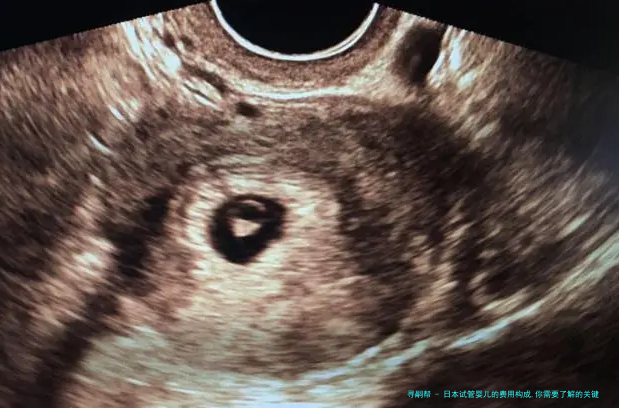

日本试管婴儿技术在全世界声誉卓著,吸引了很多夫妻前往求医。然而,认识日本试管婴儿的费用构成是每位求医生必须留意的关键点。下列是关于日本试管婴儿费用构成的细致说明。

3. 手术费用:试管婴儿手术囊括、胚胎培育和胚胎移植等环节。手术费用约为3万至5万元。